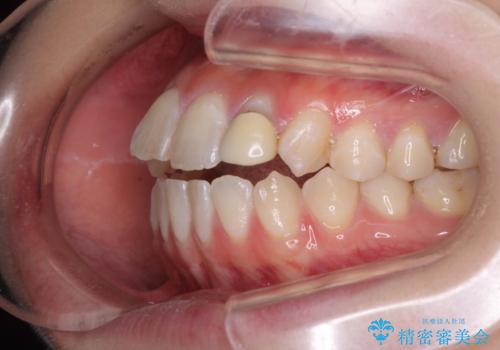

開咬を治す インビザラインによる矯正治療

- 上下前歯の開咬を気にして来院された患者様です。

開咬はインビザラインを用いると有意に改善ができるため、インビザラインによる矯正治療を行うこととしました。

途中1年8ヶ月ほど来院されず、久しぶりの来院後は治療が面倒とのことで、前歯の叢生や隙間に不十分な点が残った状態での終了となりました。